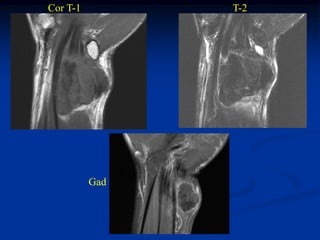

Case #253.2               Desmoid tumor

56 yr male with tender soft tissue mass volar aspect of wrist 6 mos

Cor T-1         T-2

Gad

Axial T-1   T-2